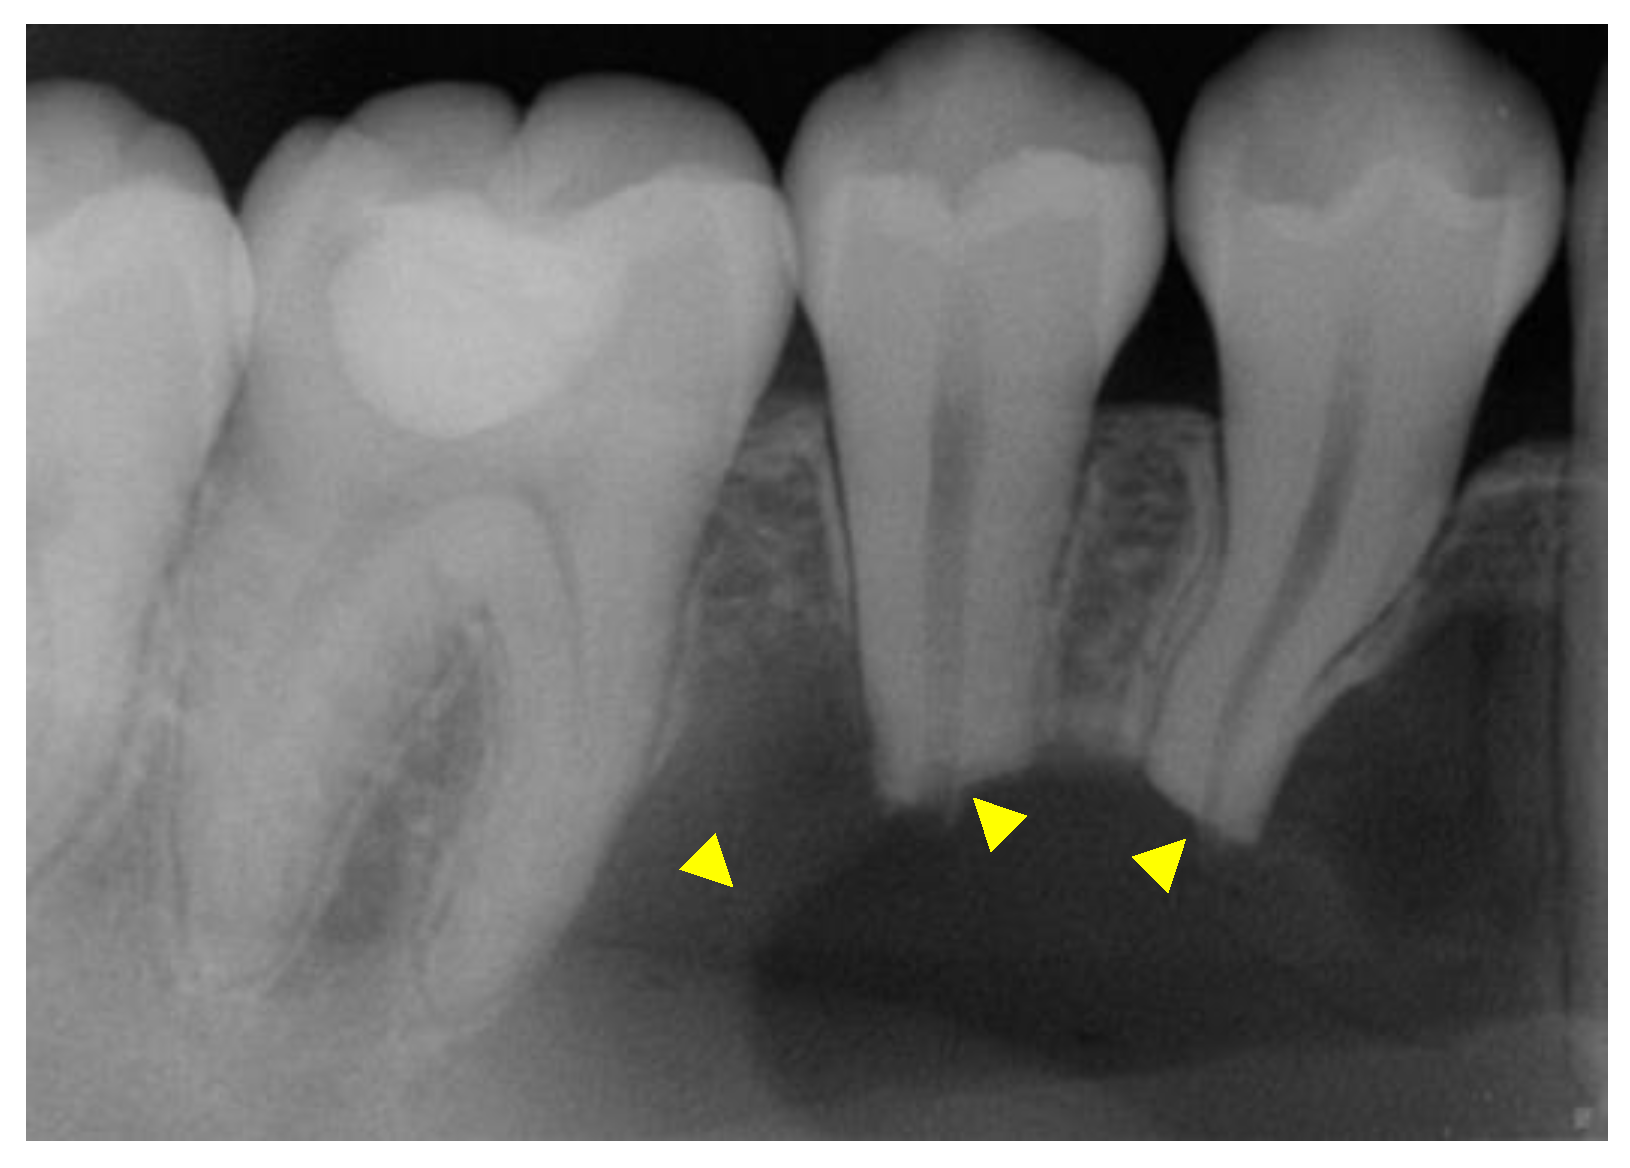

After the initial clinical examination, an intraoral periapical radiograph was acquired (Figure 2) and the patient was referred to Oral and Maxillofacial Surgery (OS) for further evaluation.

Figure 2. The yellow arrowheads show the unilocular intrabony lesion. There is evidence of root resorption in the apical third of the roots.